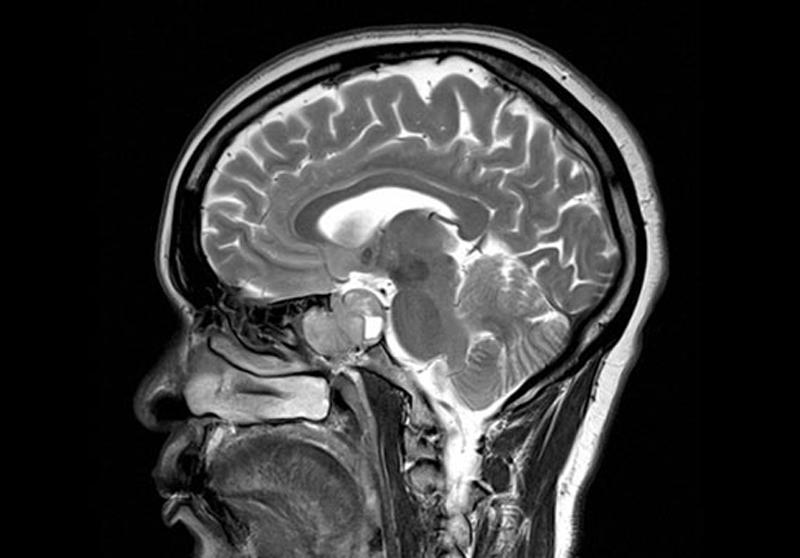

Микроаденома симптомы

Микроаденома симптомы 112 фото